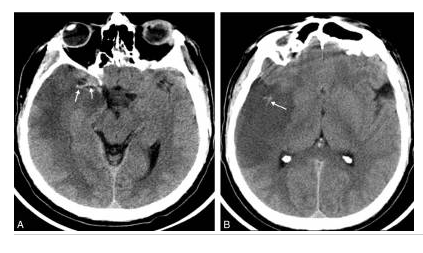

Hématome lobaire chez un sujet jeune non hypertendu en scanner.

Coupe axiale sans injection (A) : hyperdensité spontanée temporale droite responsable d’un effet de masse important. L’angioscanner (B) retrouve une prise de contraste serpigineuse (flèches) à la partie antéro-latérale de l’hématome correspondant à une malformation artérioveineuse.